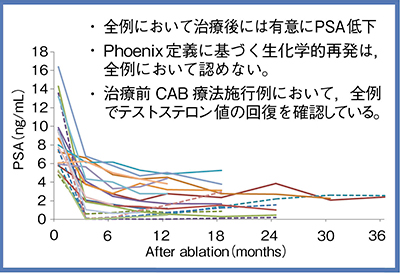

当科では2010年から前立腺の片葉小線源治療を行ってきた。適応基準および治療法を図3に示す。対象症例は,年齢の中央値が71歳,リスク分類はlowが12名,intermediateが11名の計23名である。術後のPSA値は全例で改善しており,Phoenix定義に基づく生化学的再発は全例において認めていない(図4)。排尿機能は術後早期に一過性の増悪があるが,1年ほどで治療前のレベルに回復。性機能も治療前後でほとんど変化は認めず,治療前に良好な機能を示す症例では,射精を含めた全性機能が温存された。

図4 前立腺片葉小線源療法後のPSA値の推移